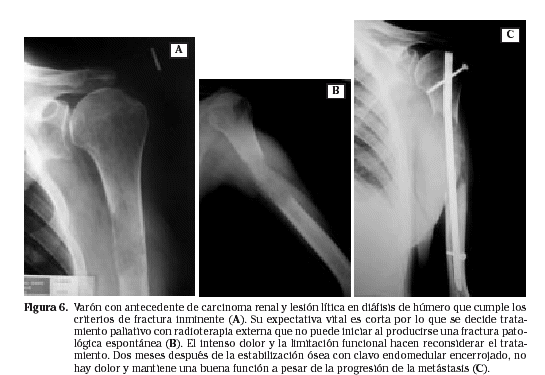

En las metástasis óseas diafisarias el tratamiento consiste en una ostesíntesis lo más amplia y estable posible del hueso, que cubra todas las áreas de debilidad, anticipándose incluso a la progresión previsible de la enfermedad (Figs. 5 y 6).

Ya en la década de los 50-60 comienzan a aparecer trabajos en los que se enfatiza sobre las ventajas que proporciona la fijación interna de las fracturas patológicas con respecto a los clásicos procedimientos de reposo en cama durante largos períodos de hospitalización y ortesis o aparatos de inmovilización externa más o menos complicados. Proponían la estabilización de las fracturas patológicas con clavos intramedulares y el empleo de estos métodos de forma profiláctica en algunos casos de lesiones líticas con amenaza de fractura, asociando radioterapia postoperatoria, es decir, las mismas bases del tratamiento actual con los materiales y procedimientos de la época. Los resultados en la mejoría del dolor y la función inmediata ya eran esperanzadores19.

La introducción posterior de los clavos endomedulares encerrojados supuso un salto cualitativo, mejorando la estabilidad rotacional y global del montaje, evitando el colapso en el defecto óseo originado por la metástasis mediante una intervención corta, segura y poco agresiva, pues no precisaba el abordaje del foco y permitía la radioterapia temprana al estar las cicatrices alejadas del área a irradiar.

Giannoudis, utilizando clavos encerrojados en 30 fracturas patológicas e inminentes de la diáfisis del fémur, consigue la estabilidad suficiente para la movilización sin dolor o con mínimas molestias en todos los casos49. Otros autores presentan casuísticas con similares resultados50,51. Ocurre lo mismo al aplicar la técnica en la diáfisis humeral18.